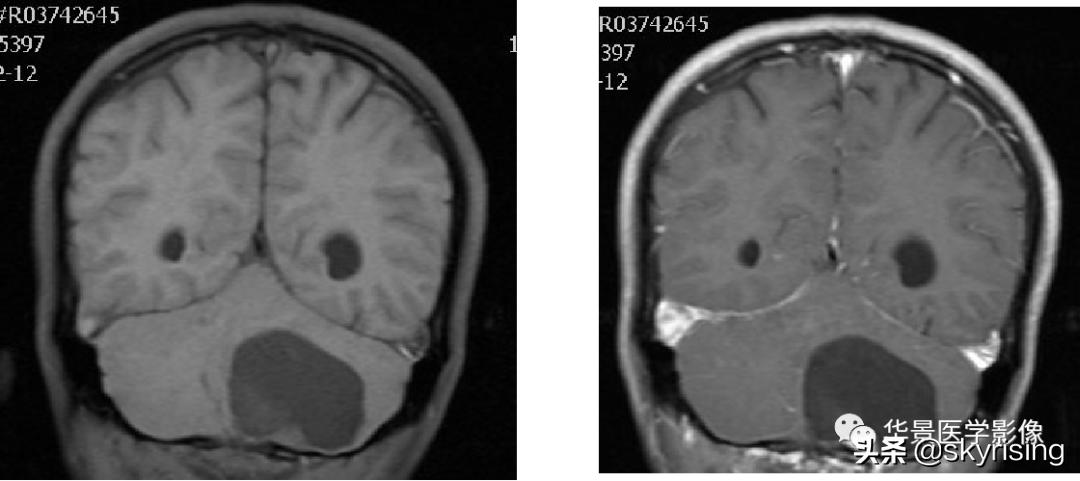

上图白色箭头:小脑延髓池内延髓背侧不规则形团块影,小脑半球、延髓、第四脑室受压变形,所见诸脑室未见增宽。

蓝色箭头:延髓受压前后径变窄,T1信号减低,考虑合并水肿。

黄色箭头:病灶边缘见流空信号血管影。

小脑延髓池内见不规则异常信号影,呈长T1长T2信号,内部信号不均,边缘见稍粗大流空信号血管影,FLAIR少许片状低信号,增强呈明显强化,DWI不均质低信号,ADC不均质高信号。小脑半球、延髓、第四脑室受压变形。临近延髓变窄,呈长T1长T2信号。